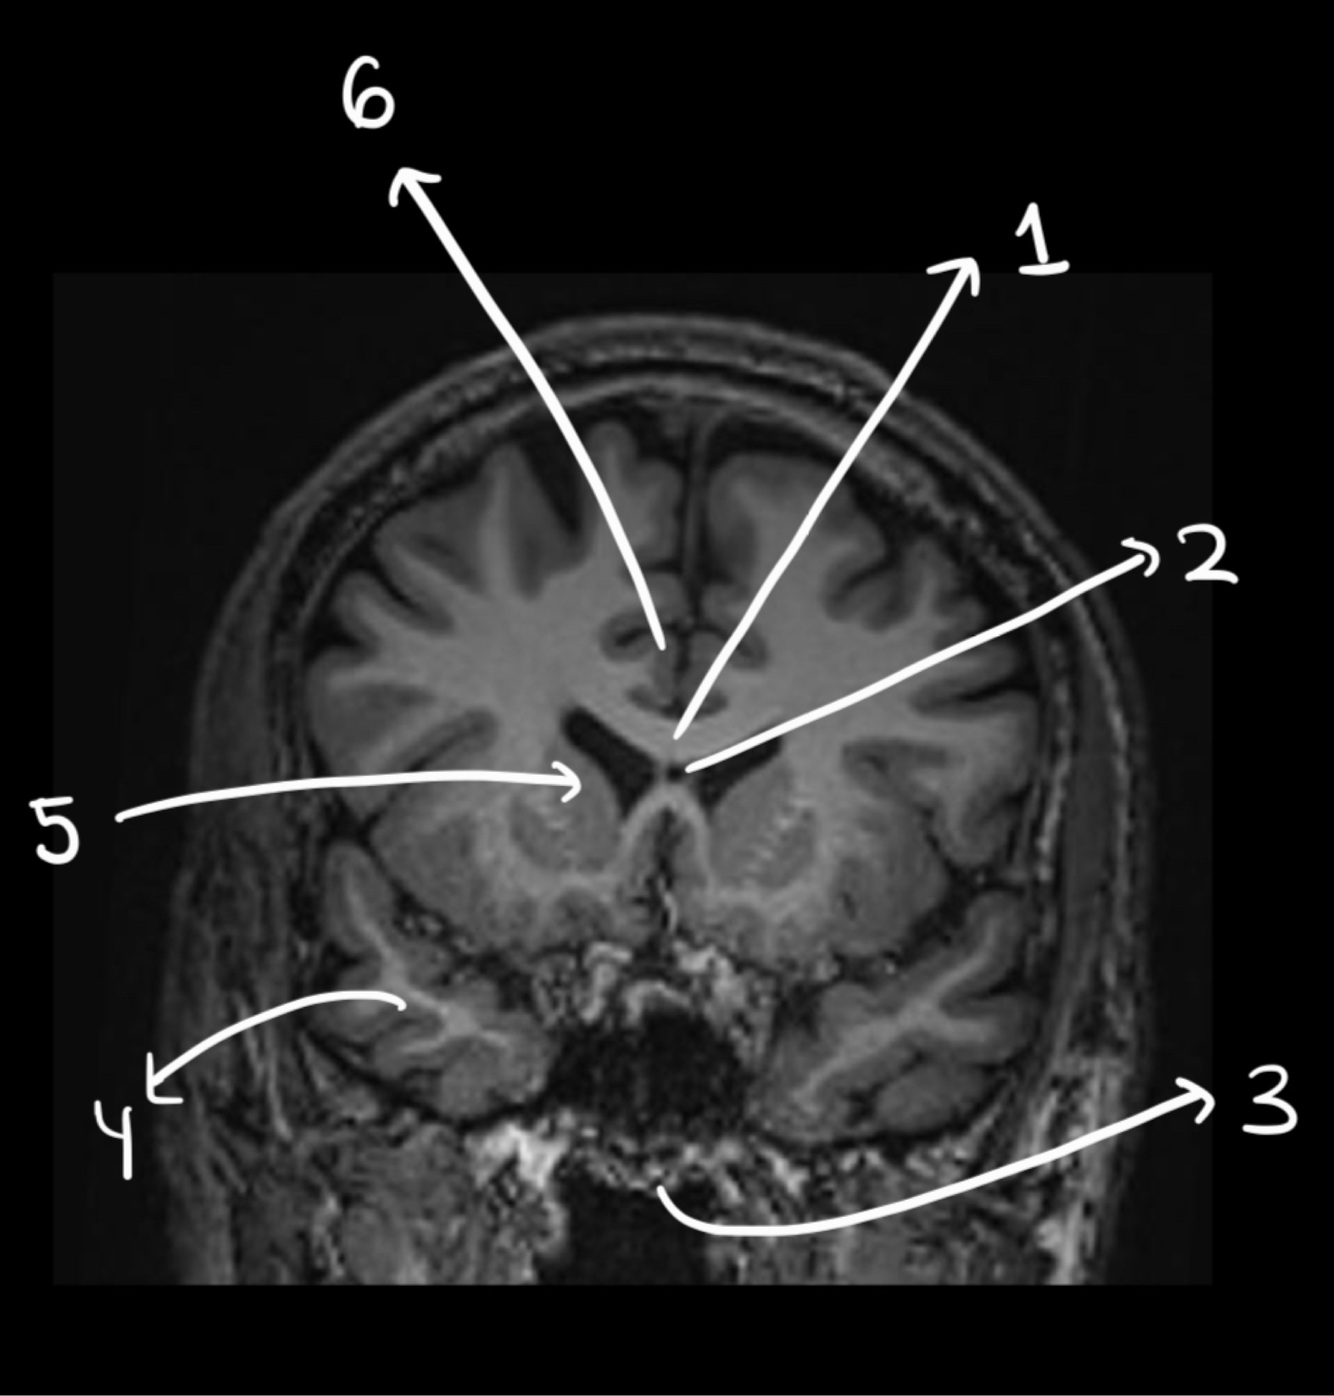

Name the structure

Hypophisis